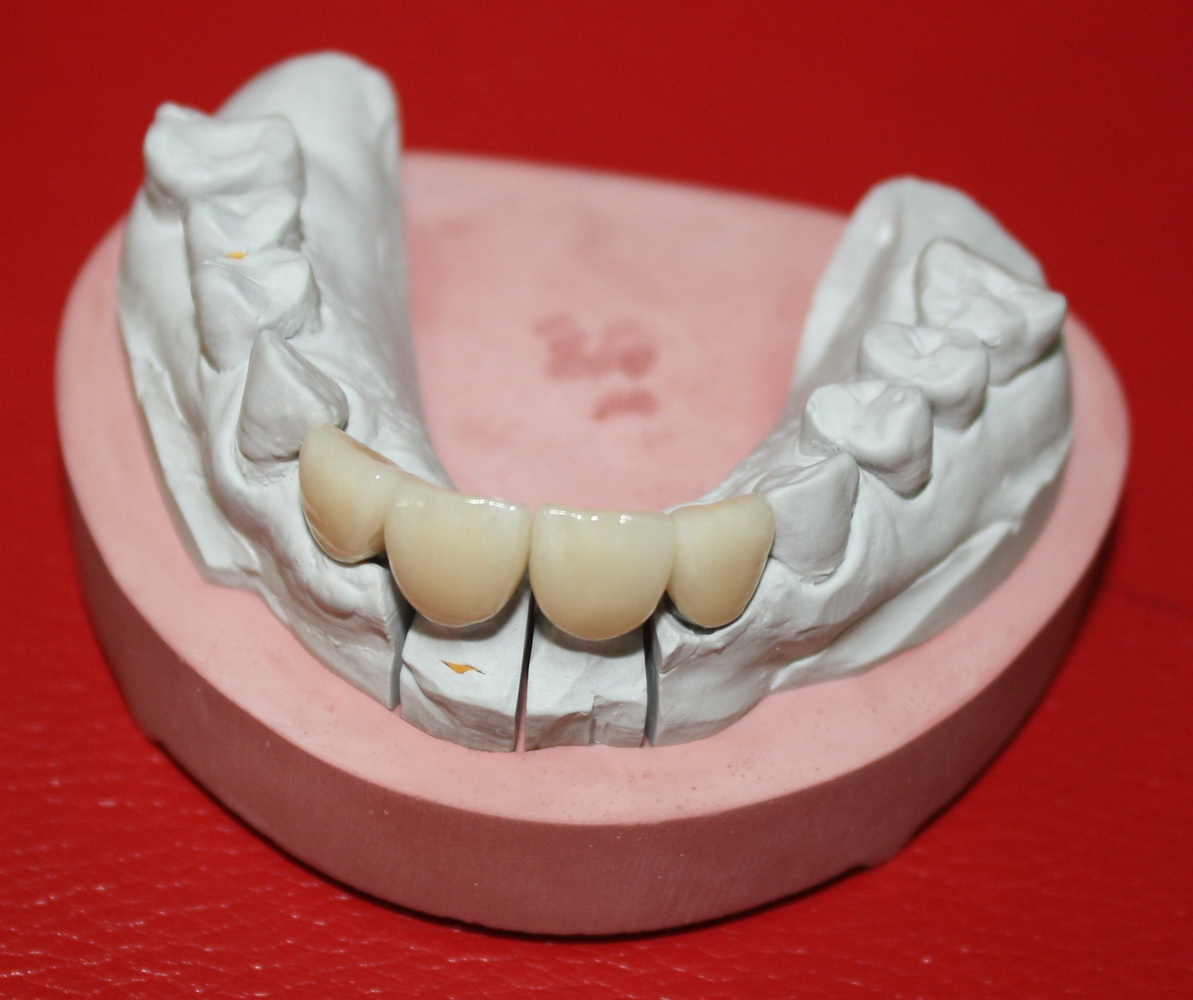

Писал статью для пациентов, но получилась статья или для «продвинутых» пациентов, или для начинающих врачей. Прочитайте и определитесь, кто Вы))).